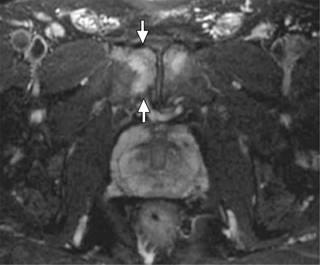

Podemos realizar una primera aproximación diagnóstica solicitando una radiografía de pelvis, con proyecciones anteroposteriores y axiales, por su facilidad y coste a la hora de realizarse. Comúnmente, evidenciaremos esclerosis subcondral, irregularidad de la sínfisis y resorción ósea, en casos avanzados (Figura 1).8 La prueba que mayor información nos va a aportar será la resonancia magnética (RM). Será frecuente encontrarse un edema medular difuso, el cual se extiende desde la superficie subcondral, que a menudo involucra ambas ramas púbicas.9 Además, se suelen encontrar signos de periostitis, irregularidades de las superficiales articulares, erosiones, osteofitos anteriores y posteriores y quistes subcondrales. El signo de la herradura está comúnmente presente (Figura 2). Las uniones miotendinosas se conservan, a menos que haya tendinopatía coexistente.9